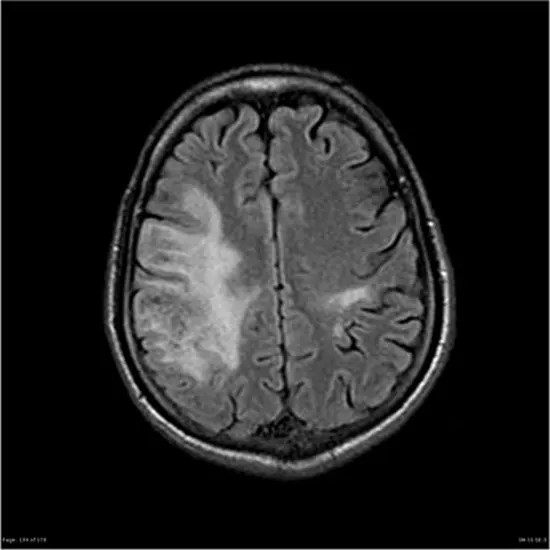

PML appears on CT as a low-density, confluent lesion without mass effect, contrast enhancement, or risk of herniation. On MRI, they appear as areas of decreased signal on T1-weighted images. Contrast-enhanced MRI shows hyperintense lesions on T2-weighted images, especially in subcortical lesions, periventricular regions, and lesions confined to the cerebellum.

On PML-IRIS, patients show worsening neurological status after initiation of ART or after dose reduction of immunosuppressive therapy, followed by contrast enhancement, edema, and inflammatory changes indicative of mass effect on MRI images. . Similar her MRI findings are seen in her patient who developed PML after natalizumab treatment.

Although similar in appearance to PML, PML is radiologically asymmetric, well-demarcated, non-enhancing with no mass effect, whereas both Toxoplasma gondii and PCNL present as contrast-enhancing lesions. Also, his CSF testing at PCNL may show a positive result for Epstein-Barr virus.

However, radioimaging is markedly different and may help identify natalizumab-induced PML. PML lesions are larger, hyperintense, and solitary compared to the multifocal, hypointense nature of typical MS lesions.